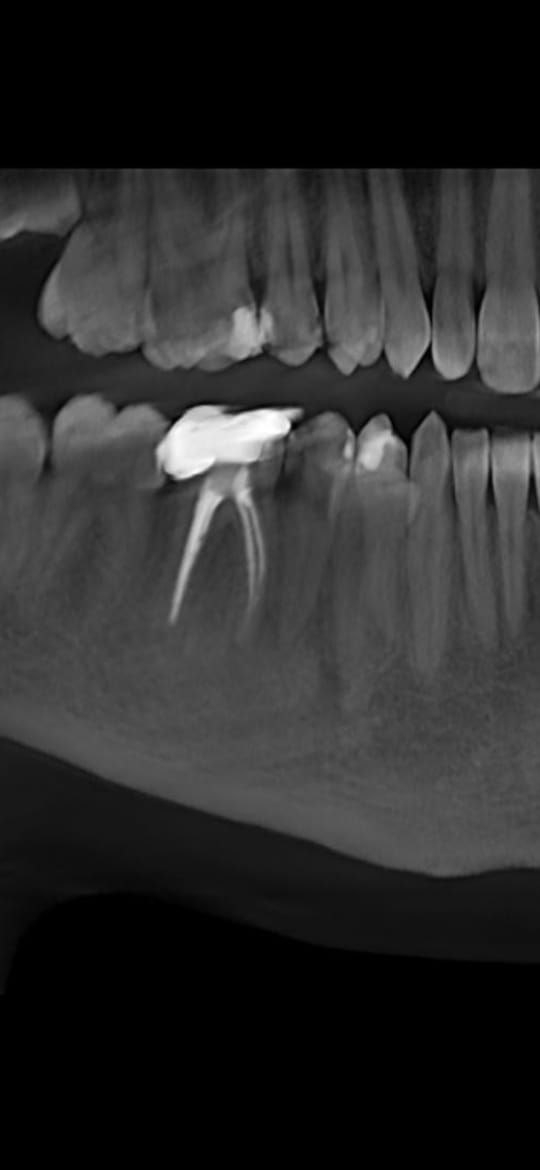

960x1280

>>1657604

Вот даже кусок старого рентгена остался трёхлетней давности

Сапдвач а кто-то из шарящих на доске есть?

Нужна будет имплантация переднего верхнего + постановка 2х коронок по обе стороны импланта. С одной стороны зуб перелечивали, восстановили коронковую часть и терапевт сказала моя работа здесь закончена.

Второй зуб пикрил спереди и с обратной стороны как выглядит. Был восстановлен лет 8 назад пломбой + вкладкой, половина зуба (меньшая его часть слева на фотке спереди) родная остальное пломба, спереди как видно кариес под ней нарисовался + с обратной стороны пиздец нагромождение массы даже не уверен что там родное а что пломба + приклеен к соседнему кривому. Терапевт сказала что пролеченные корни на КТ с виду норм у него.

Вопрос: при установке коронок ортопед обтачивает зубы или мне нужно опять к терапевту привести в человеческий вид оба зуба с фотки до ортопеда и терапевтом же их обточить?

И вопрос по имплантации, насколько критично делать в одной и той же клинике имплант + обе коронки? Передние зубы как никак, эстетика очень важна. Медентика норм имплант или лучше на астра тек\штрумана раскошелиться? И какие подводные в формировании стоимости коронок? Внятного ценника не могу найти, везде "От", в лучше случае указано порядка 30-35 за циркониевые\е-максы но непонятно то там сверху по доп работам встанет.